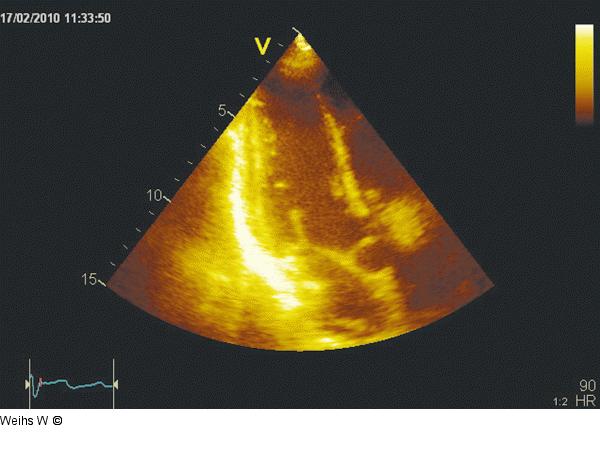

Abbildung 3: Apikaler Längsschnitt Im apikalen Längschnitt zeigen eine gute systolische Linksventrikelfunktion, eine unauffällige Mitral- und Aortenklappe sowie ein normal großer linker Vorhof. |

Im apikalen Längschnitt zeigen eine gute systolische Linksventrikelfunktion, eine unauffällige Mitral- und Aortenklappe sowie ein normal großer linker Vorhof. |